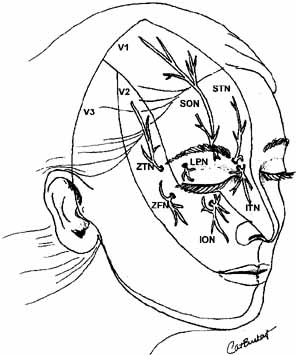

Fig. 20 Cutaneous distribution of V1 and V2 nerves. (V1, V1 nerve; V2, V2 nerve; SON, supraorbital nerve; STN, supratrochlear nerve: ITN, infratrochlear nerve; ION, infraorbital nerve; LPN, lateral palpebral nerve; ZFN, zygomaticofacial nerve; ZTN, zygomaticotemporal nerve) Fig. 20 Cutaneous distribution of V1 and V2 nerves. (V1, V1 nerve; V2, V2 nerve; SON, supraorbital nerve; STN, supratrochlear nerve: ITN, infratrochlear nerve; ION, infraorbital nerve; LPN, lateral palpebral nerve; ZFN, zygomaticofacial nerve; ZTN, zygomaticotemporal nerve)

|